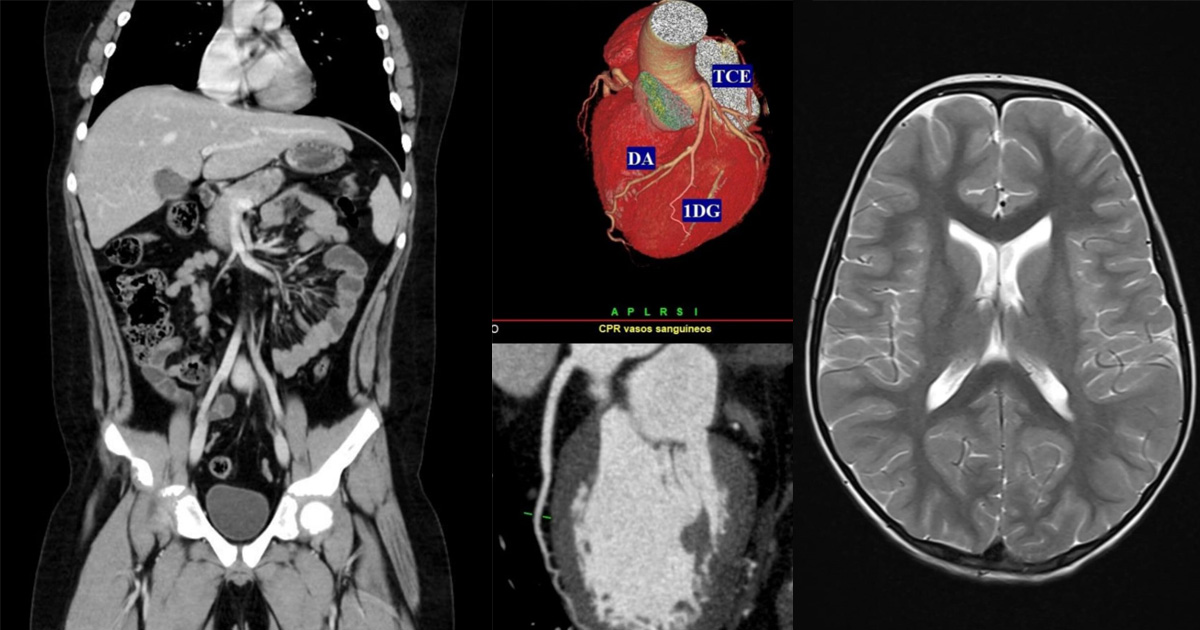

Tomografia Computadorizada: mais de 12 mil exames anuais, com um tomógrafo atual de 64 canais, com algoritmos avançados de reconstrução que geram 128 imagens por rotação, o que garante altíssima definição, menor dose de radiação e oferece conforto e segurança ao paciente, com maior precisão diagnostica.

Ressonância Magnética: mais de 9 mil exames em 2024, sem radiação, para detecção precisa de aneurismas, lesões do sistema nervoso central, alterações abdominais e lesões articulares.

De acordo com Dra. Jaicer, “a aquisição recente do novo tomógrafo de alta resolução, o único da cidade e um dos únicos da região, possibilitou a incorporação ao Serviço de uma nova modalidade de exame, a angiotomografia computadorizada de coronárias, as artérias do coração, capaz de ajudar a prevenir eventos cardíacos súbitos e fatais”. Além disso, o Serviço também realiza atualmente Ressonância Magnética Cardíaca, possibilitando complementação diagnóstica em casos específicos.